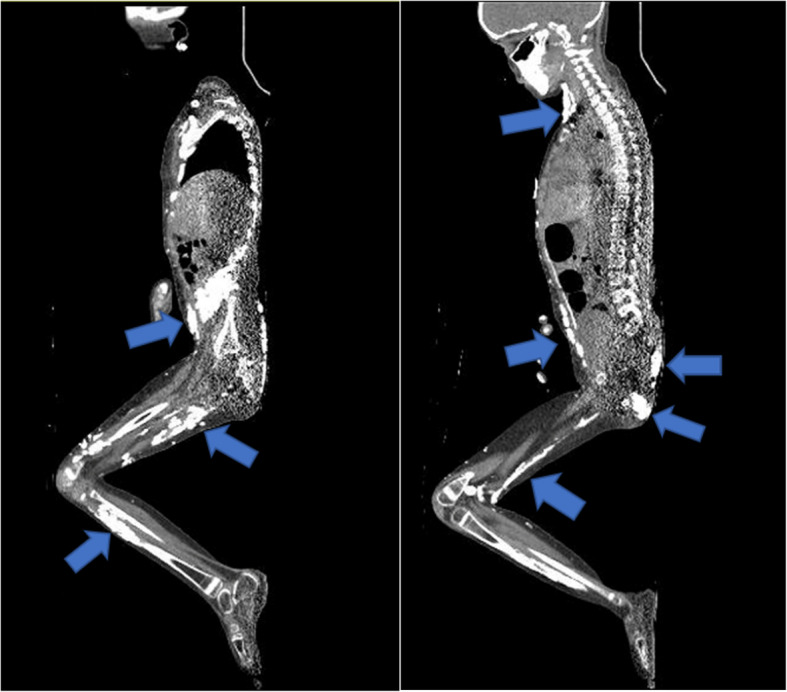

Calcinosis is a severe manifestation of juvenile and adult idiopathic inflammatory myopathies, which can lead to pain, limited range of motion, disfigurement, and infection. It is more common in juvenile idiopathic inflammatory myopathies, especially in juvenile dermatomyositis (JDM). Calcinosis can be visible on cutaneous surfaces, although can also present in muscles and internal organs, making a thorough assessment difficult without imaging modalities. In this narrative review, we discuss different imaging modalities used in evaluating JDM-associated calcinosis including X-ray, computed tomography (CT), magnetic resonance imaging (MRI), and ultrasound (US).